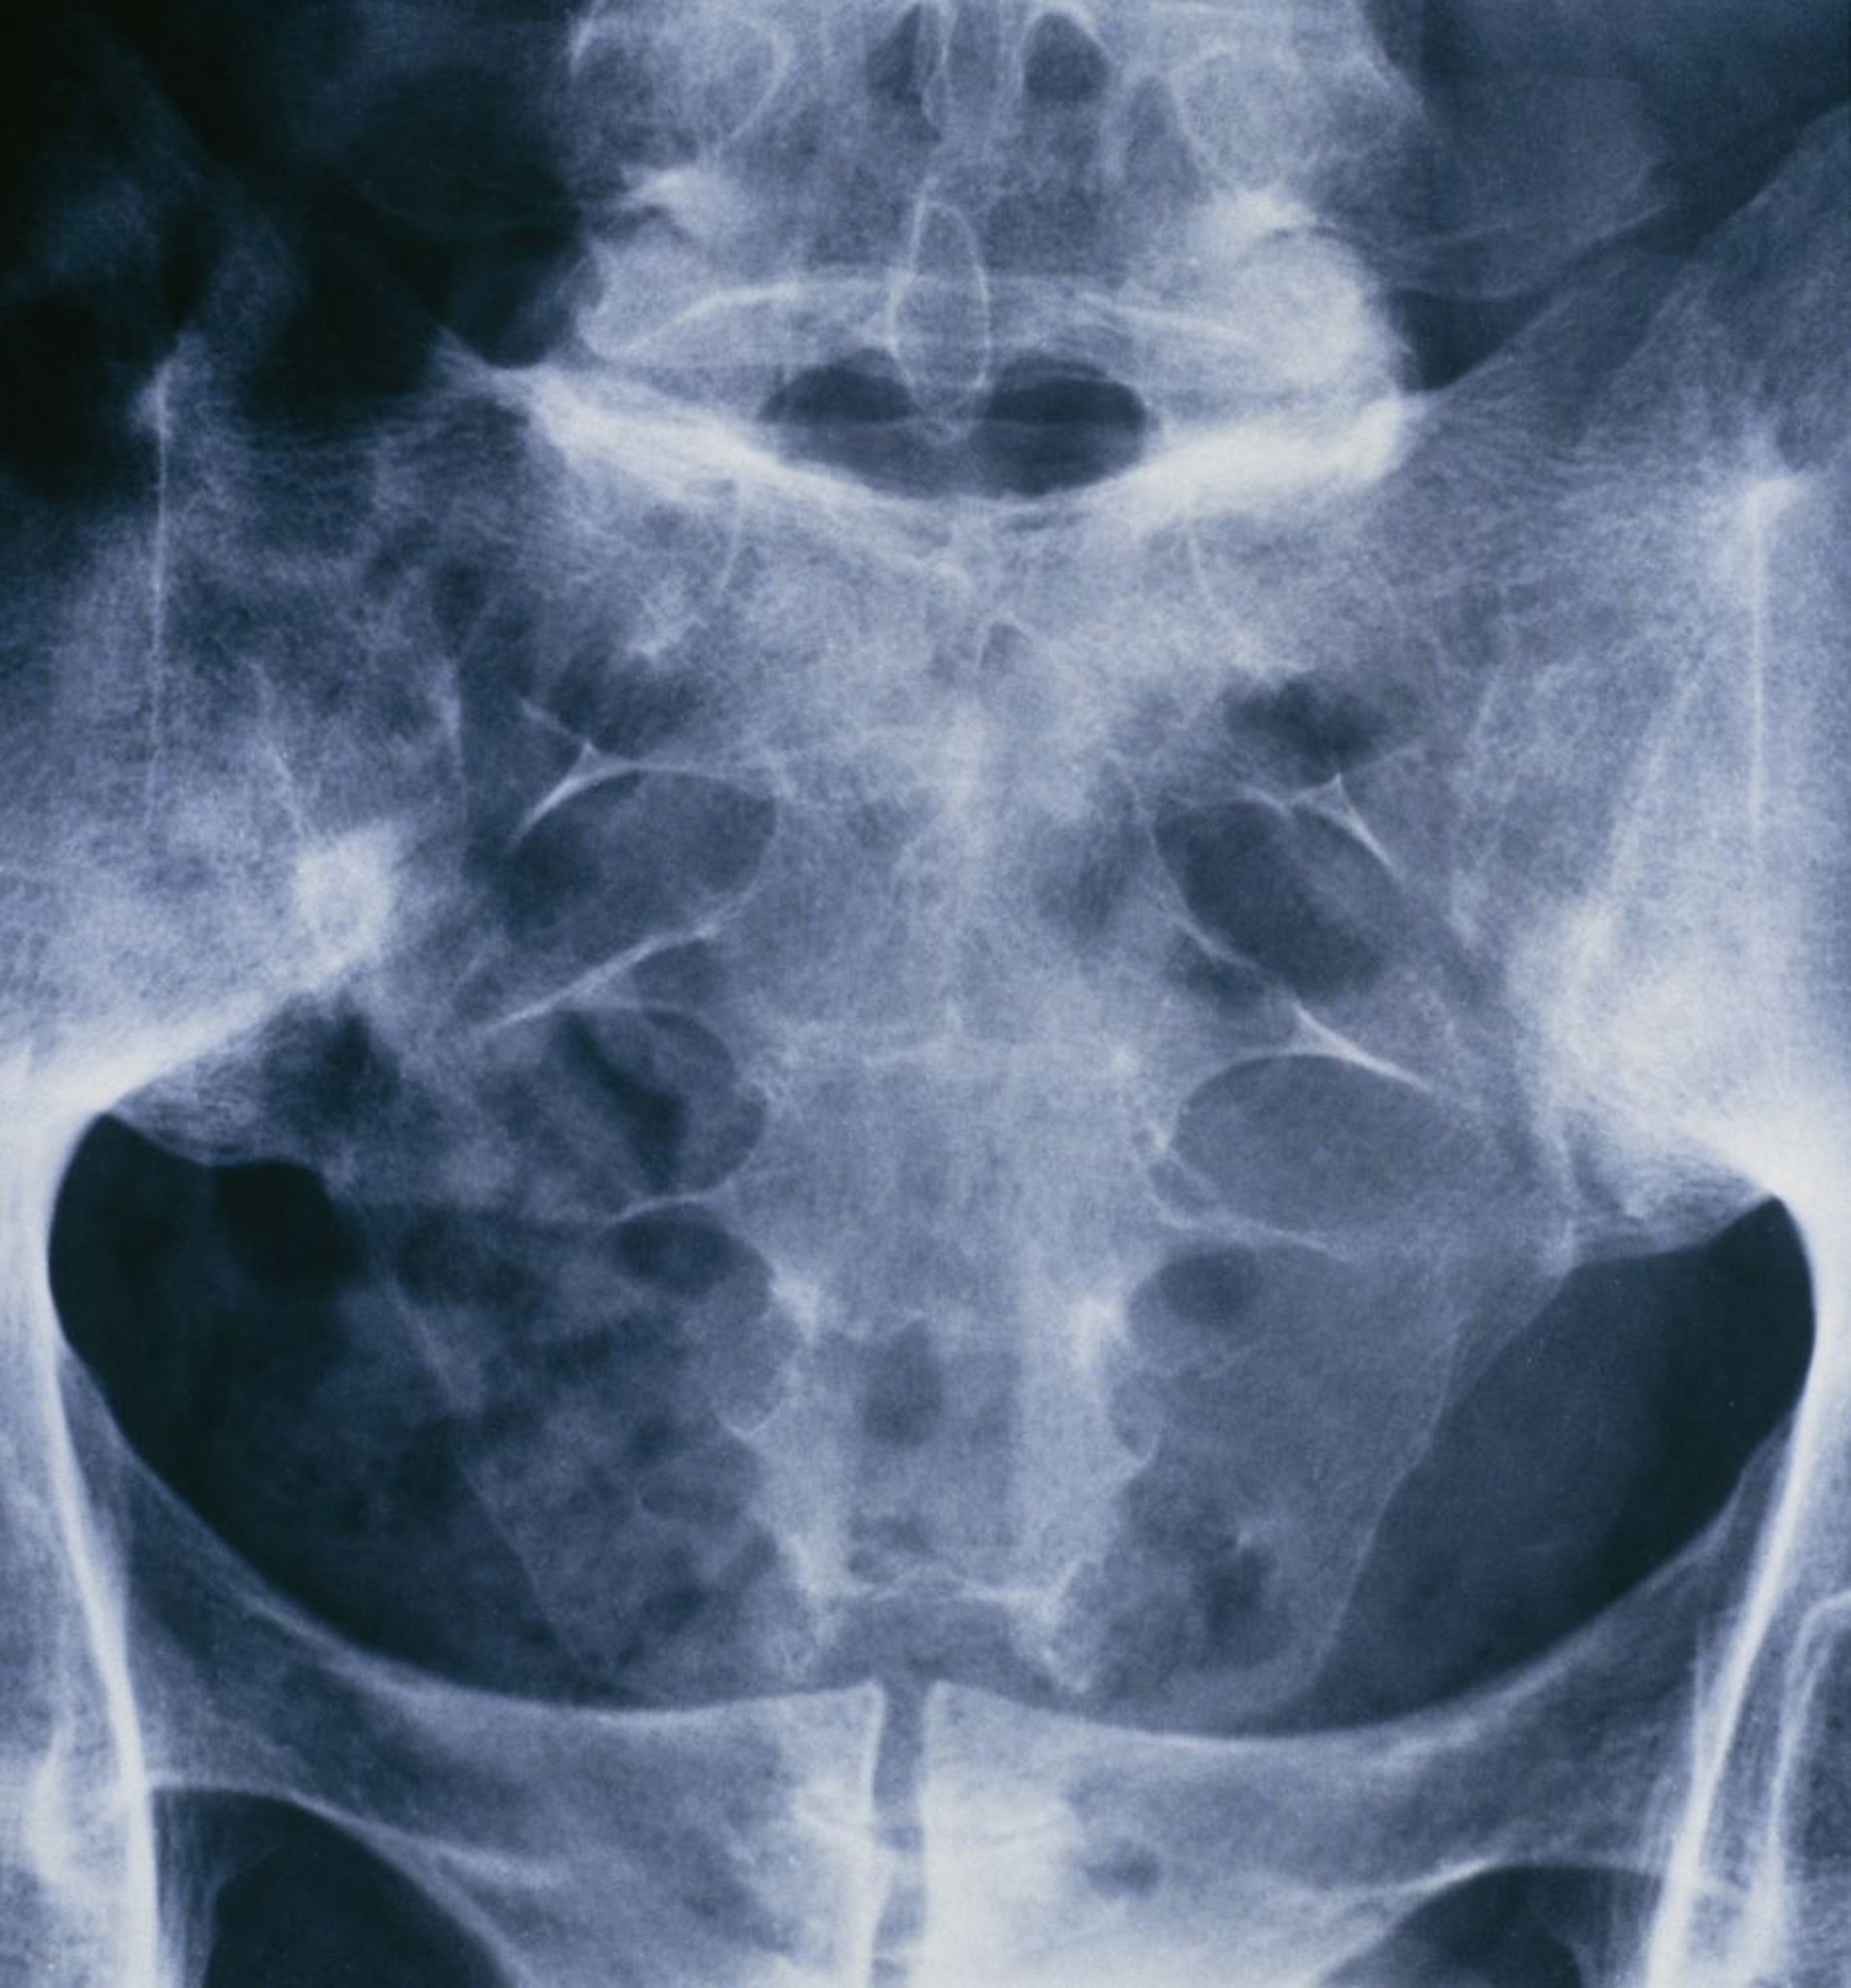

Viêm cột sống dính khớp (viêm khớp cùng chậu)

Phim X quang xương chậu và cột sống cùng này của một người bị viêm cột sống dính khớp cho thấy tình trạng hợp nhất của cả hai khớp cùng chậu.

ST. BARTHOLOMEW'S, LONDON/THƯ VIỆN HÌNH ẢNH KHOA HỌC